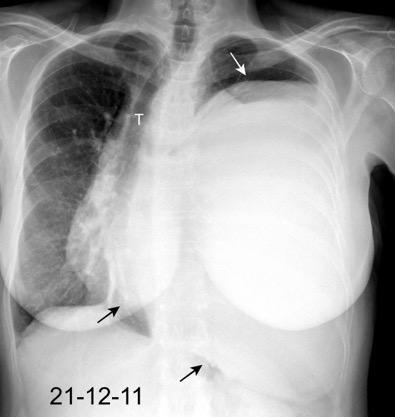

Accidente de tráfico

Rx: Niveles hidroaéreos en hemitórax izquierdo Desviación mediastínica Ausencia de intestino en abdomen. Configuración en reloj de arena del intestino herniado “Tubo nasogástrico”

Furak J et al. Diaphragm and transdiaphragmatic injuries. J Thorac Dis 2019

Recibe una puñalada en costado izquierdo

La laceración tiende a ocurrir en la unión

músculotendinosa . (64-90% en el lado izquierdo)

Diafragma “colgante” (“dangling sign”)

(“Dangling sign”)

TC. Mejor con multicorte. (reconstrucciones).

Asociación: Aire en pared.

Fracturas costal .Rotura esplénica. Neumoperitoneo.

Diafragma discontinúo Herniación de la grasa omental

Desser TS et al.The dangling diaphragm sign: sensitivity and comparison with existing CT signs of blunt traumatic diaphragmatic rupture. Emerg Radiol 2010